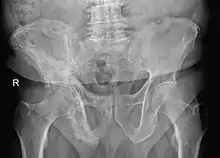

Paget's disease of right innominate bone. Man of 80 years age.

Paget's disease may be diagnosed using one or more of the following tests:

• Pagetic bone has a characteristic appearance on X-rays. A skeletal survey is therefore indicated.